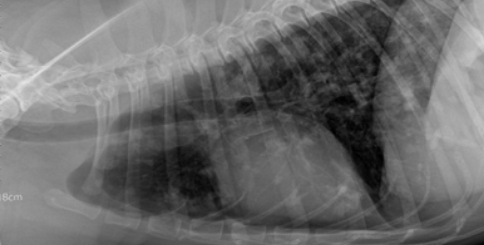

X-ray 검사

X-ray 검사는 초음파 검사나 CT 검사와 같은

심화 영상검사를 진행하기 전에 복부, 흉부, 근골격계를

전반적으로 평가할 수 있는 비교적 쉽고 간단한 검사입니다.

눈으로 직접 확인하기 힘든 장기들을

밀도의 차이로 영상화하여 크기, 모양, 위치,

밀도 변화를 확인하는 검사 방법입니다.